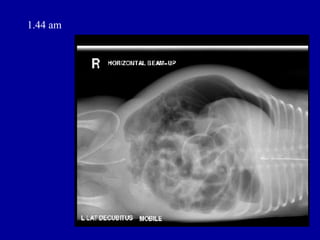

1.44 am

ORIGINAL REPORT • HISTORY • NEC, septic shock on CPAP, IA and IV lines. • REPORT • AXR - SUPINE AP • Compared with AXR taken 10 hours earlier. • The nasogastric tube is now seen projected over the left hypochondrium. There is • interval worsening of the gaseously distended intestinal loops. Faecal matter is • again seen in the proximal colon. No air or faecal matter seen in the pelvic cavity. • There is free extraluminal air within the peritoneal cavity, outlining the liver. • Rigler's sign is noted, consistent with intestinal perforation.